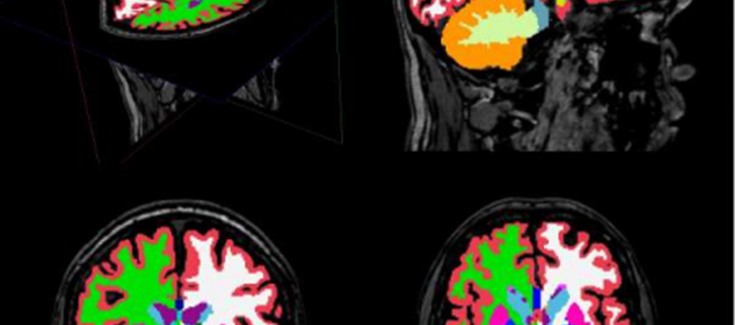

Para solventar estos problemas e intentar clarificar el tipo de anomalías estructurales cerebrales presentes en la esquizofrenia, se ha llevado a cabo un innovador meta-análisis prospectivo que analiza datos de imagen cerebral obtenidos mediante resonancia magnética. Se trata del mayor estudio colaborativo de imagen cerebral en pacientes con esquizofrenia realizado hasta la fecha, en palabras de Benedicto Crespo Facorro.

En este estudio, en el que se incluye muestra de psicosis PAFIP, se analizaron datos de resonancia magnética cerebral de 2.028 pacientes con esquizofrenia y 2.540 individuos sanos obtenidos mediante métodos estandarizados en 15 centros de investigación de diferentes países. En comparación con los controles, los pacientes con esquizofrenia mostraron una disminución en el volumen del hipocampo (estructura asociada con la memoria), la amígdala (estructura asociada con la emoción), el tálamo (asociado a la actividad sensorial) y del núcleo acumbens. Asimismo presentaron un aumento en el volumen del pállidum (involucrado en la motivación y la emoción) y de los ventrículos laterales.

Además, se encontró una asociación entre los volúmenes del putamen y del pállidum y la duración de la enfermedad y que el déficit en el volumen del hipocampo era más severo en las muestras con mayor proporción de pacientes sin medicar. Esto sugeriría, según Crespo-Facorro, que "el tratamiento con antipsicóticos podría aminorar la pérdida de volumen en el hipocampo". La consistencia entre los resultados encontrados en este estudio y los descritos anteriormente mediante métodos de análisis tradicional validan la metodología desarrollada por el consorcio ENIGMA. "Se está intentando aplicar una metodología similar al estudio de la corteza cerebral en pacientes con esquizofrenia. También se han iniciado colaboraciones para estudiar el efecto que pueden tener en el cerebro factores como el consumo de drogas, el ejercicio físico o el estrés", ha explicado Roberto Roiz, investigador del CIBERSAM.